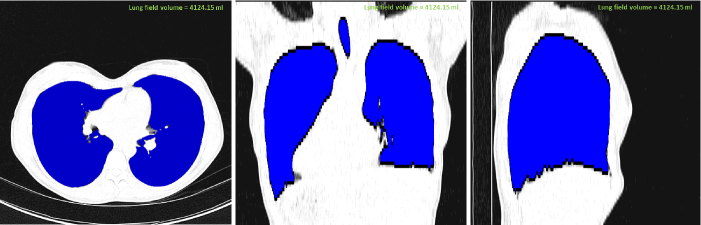

where \mathcal{L} denotes the location of the voxel(s), and I𝒯=Ileft𝒯Iright𝒯superscript𝐼𝒯subscriptsuperscript𝐼𝒯𝑙𝑒𝑓𝑡subscriptsuperscript𝐼𝒯𝑟𝑖𝑔𝑡I^{\mathcal{T}}=I^{\mathcal{T}}_{left}\cup I^{\mathcal{T}}_{right}. In addition to the seeds, the FC algorithm requires the mean m𝑚m and the variance σ𝜎\sigma of the target region(s). These values are empirically adjusted in the software to the default values corresponding to normal lung parenchyma, i.e., m=550𝑚550m=-550 HU, and σ=150𝜎150\sigma=150 HU after analyzing hundreds of CT images from wide variety of sources. Once the seeds are identified and parameters adjusted, FC delineation is performed. It is important to note here that, the entire procedure is performed in the user interface using a single click unless users prefer to input seed location themselves. Fig. 3 shows the annotation produced by CIDI-Lung-Seg in axial, coronal, and sagittal planes. Fig. 4 shows 3D rendering of the annotation using the software’s rendering module.

Refer to caption

Figure 3: Annotated lung (shown in blue) from CT image viewed in CIDI-Lung-Seg (a) axial plane, (b) coronal plane, and (c) sagittal plane.